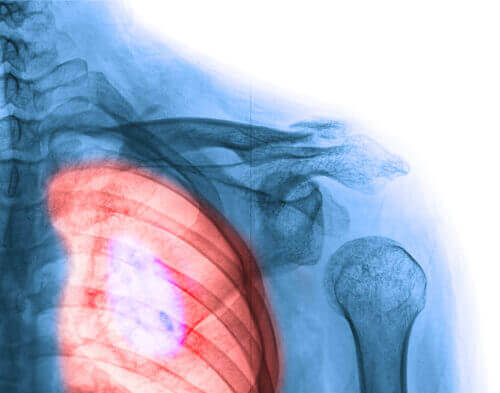

4. Рак легенів

Це однин з найчастіших видів раку у жінок. Тим не менше, в останні кілька років, частота захворюваності стала доволі високою, і це тривожить, адже цей вид раку має один з найвищих показників смертності, як у чоловіків, так і жінок.

У 80% випадків причиною є, звичайно, куріння. Навіть перебування в місцях або ситуаціях, де тютюновий дим впливає на вас мають серйозні наслідки для вашого здоров’я. Цієї звички, безумовно, слід уникати, а також необхідно облишити інші шкідливі звички, які призводять до розвитку багатьох хвороб.

Кількість курців жінок значно зросла. Або чогось не вистачає у рекламних кампаніях або повідомлення просто не доходять до тих, кому вони призначені: позбудьтесь шкідливих звичок заради свого ж здоров’я та душевного спокою! Для раннього виявлення раку легень слідкуйте за такими симптомами:

- Постійний кашель

- Біль у грудях при кашлі

- Свист у грудях при диханні

- Втома

- Втрата ваги

- Кашель з кров’ю

- Відчуття, ніби вам бракує повітря при диханні

- Хропіння в нічний час